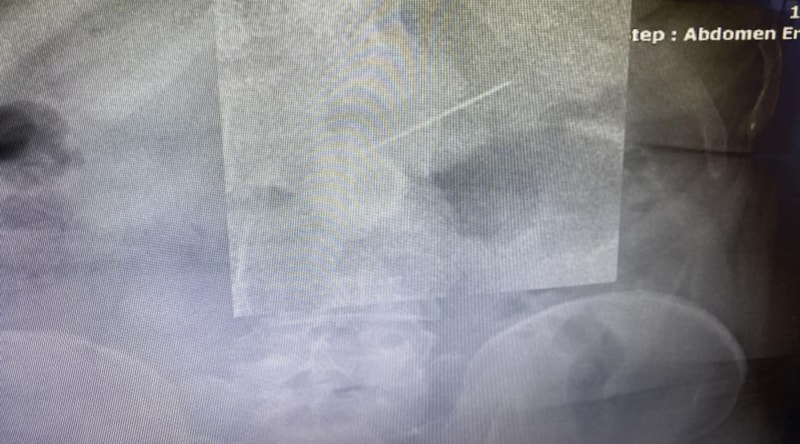

Başakşehir Çam ve Sakura Şehir Hastanesi acil servisinde tedavi altına alınan kadının, hemen film çekildi.

Toplu iğnenin mideye ulaştığı belirlenirken gerçekleştirilen endoskopik işlemle hastanın midesindeki iğne olduğu noktadan alındı.

Biz acil servilerde yaptığımız görüntülemelerde iğnenin henüz daha midede olduğunu, daha fazla ileriyle gitmediğini gördük. Akabinde hastamızı endoskopi ünitemize aldık, burada yaptığımız endoskopide de tam mide çıkışında mide mukozası dediğimiz en iç tabasına saplanmış şekilde gıda artıklarının arasında durduğunu gördük. Zor da olsa özel aletlerimizi kullanarak iğnemizi tuttuk, daha sonra endoskopi kanalının içinden hastamıza herhangi bir zarar vermeden dışarıya çıkarttık. Bu iğnenin hastamıza bu aşamaya kadar herhangi bir zarar vermediğini yemek borusunda, midesinde yırtılma yapmadığını gördük.”